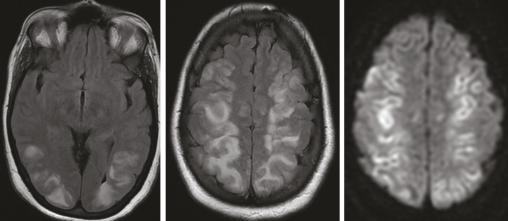

Encéphalopathie postérieure réversible

Siham Nasri, Mohammed Joudar

Cette femme de 36 ans avait une hypertension artérielle à 200/100 mmHg et une monoparésie du membre supérieur gauche post-critique, dans le cadre d’une toxémie gravidique. Une IRM encéphalique mettait en évidence des anomalies de signal cortico-sous-corticales et profondes, bilatérales et...